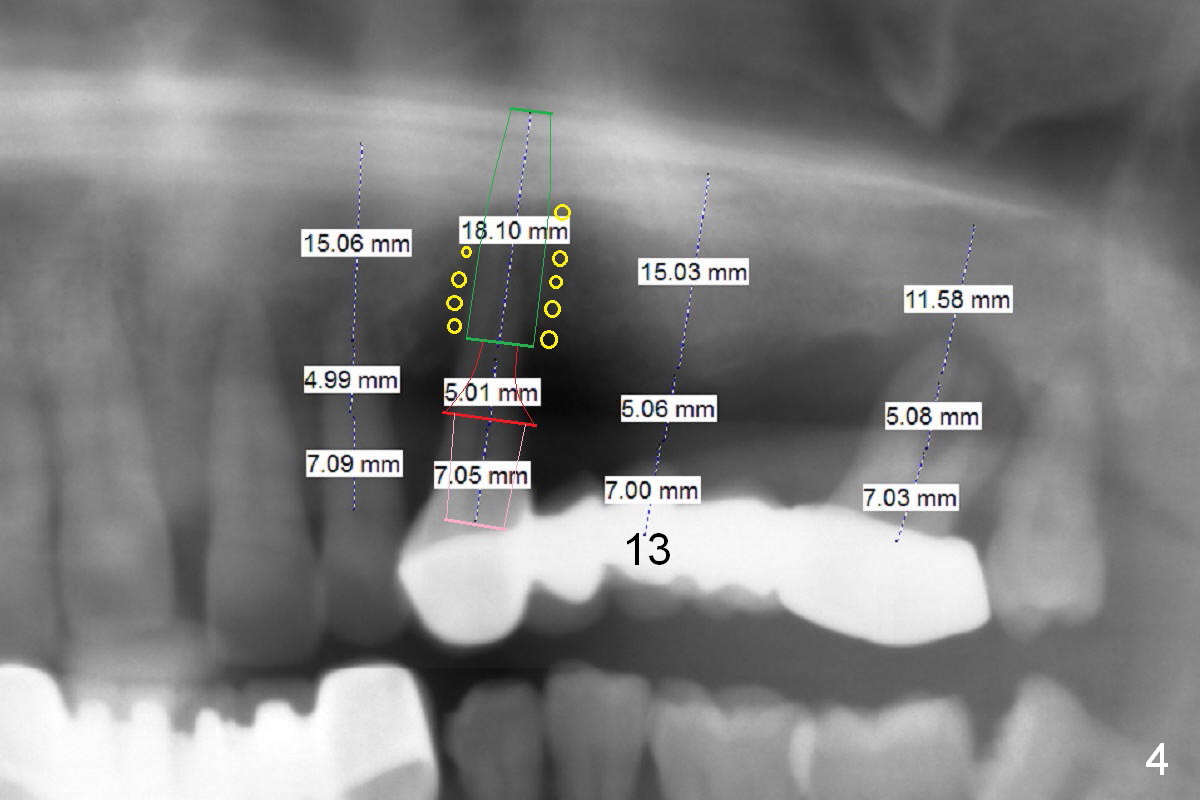

A 45-year-old man has advanced periodontitis and bruxism (sufficient remaining bone height, Fig.1). Full mouth restoration will be done by quadrant with preservation of a few of relatively healthy teeth. The 1st quadrant to be treated will be the upper left (Fig.2). The teeth #9-11 and 15 will be extracted (Metronidazole) with immediate implants. A delayed implant will be added at #13 for #11-15 bridge (Fig.4). In addition to the large radiolucency around the roots of #9 and 10 (Fig.3 red dashed line), the gingiva at #11 and 15 is excessively thick (red arrows). For example at #11, a long implant has to be placed a little more outside the bone (Fig.4 green area), since the longest cuff of the abutment (red area) is 5 mm for UF implant system. The longer the cuff, the less amount of the implant will be outside the bone with less chance of periimplantitis. When the coronal implant threads are exposed, a large amount of bone graft has to be placed (Fig.4 yellow circles).